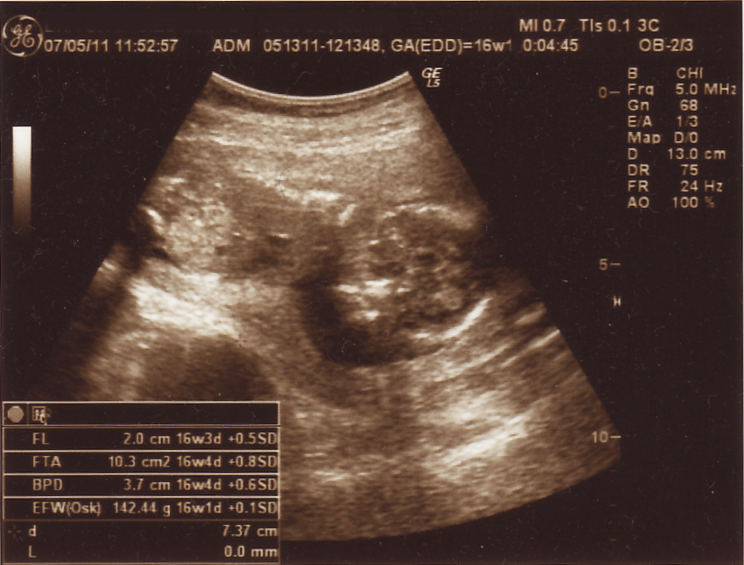

↓ 今回のエコー写真はこちら

んーーー?( ̄▽ ̄;;)

こりゃまた、なんだかよくわからないですよね。

右側が頭ってコトくらいはわかるかしら?

頭の幅とか、足の長さとか測って、推定体重が出ましたよ。

142グラム。

16週相応の大きさみたいです(^^

元気にうにゃってたので、なるべく前回の傷口はキックやパンチをしませんように・・・・お願いしたいもんです(^^